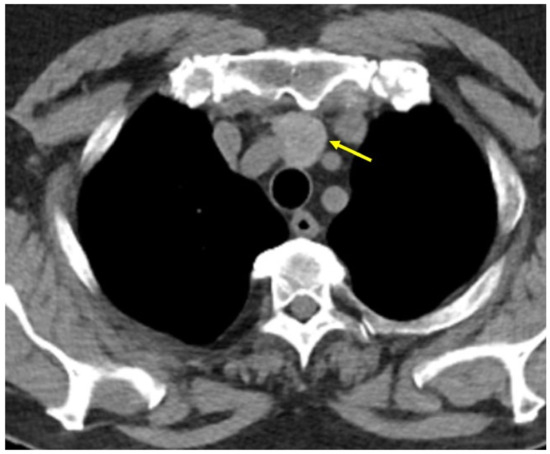

Seven months prior to current admission (while the lady started to experience some mild and intermittent breathing issues) she underwent a pneumology (including imaging) evaluation. Contrast-enhanced computed tomography (CT) showed a sub-pleural nodule of 0.5 cm in the lateral segment of the lower right lobe and a pseudo-nodular area of 1.6 by 1.4 cm, with ground glass appearance, irregular borders, and a caudal tertiary bronchus, located in the anterior segment of the upper right lobe, suggestive of underlying inflammation and infection; the trachea and main bronchi had normal aspect. Bronchoscopy and broncho-alveolar lavage revealed bronchitis, with macrophages, lymphocytes, and neutrophils, without any tumour cells. CT evaluation also revealed a nodular, hyper-dense mass, with inhomogeneous iodophilia, indicating a possible ETTM (Figure 1).

Figure 1.

ETTM first suspicion (yellow arrow) amid contrast CT evaluation: a nodular, hyper-dense mass, with inhomogeneous iodophilia, of 2 cm (transverse diameter) by 2.5 cm (antero-posterior diameter) by 3.1 cm (cranio-caudal diameter), located on the median line of the upper mediastinum, posterior to the manubrium, anterior to the trachea, inferior to the thyroid gland and superior to the aortic arch (axial plane).